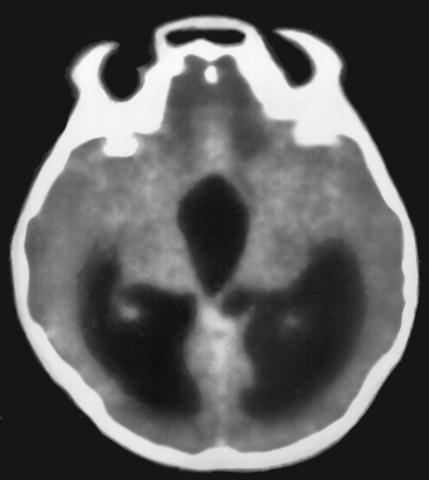

Рис. 2б). Компьютерная томограмма головы при окклюзии IV желудочка объемным процессом: расширение боковых и III желудочков.